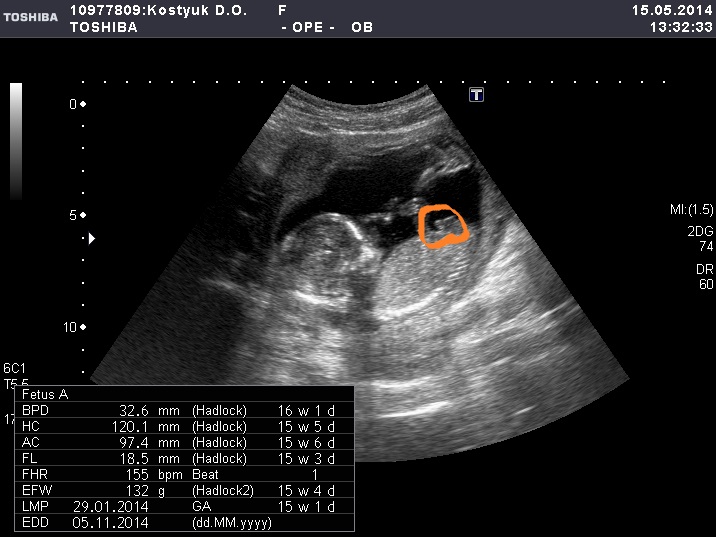

Пол малышаНам 18 неделек, решила не дождусь до скрининга и сходила на узи платно.У нас мальчишка, сыночек, солнышко мое родное!!!Состояние странное, я очень рада что по узи все хорошо слава богу.Папа наш был прав, он с самого начала говорил, что там пацик)))А я вообще не чувствовала, но наверное девочку хотелось больше, но это все такая ерунда, он мой сладенький, хорошенький, пинает мамочку, главное здоровенький.Недавно снился сон что мальчика родила, выходит вещий)))И с именем мужским давно определились, в отличии от женского.Любим и ждем тебя наш сыночек